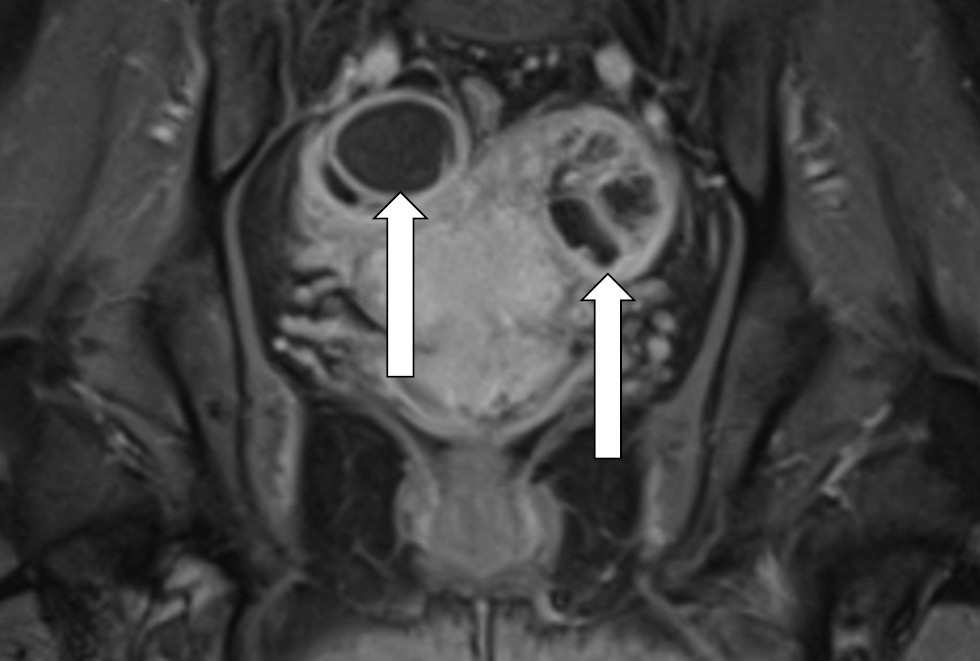

MR-presentation of adenomyosis was concluded based on the magnetic resonance imaging from 06/01/20. Ovarian cancer was questionable, as well as bilateral ovarian endometriomas and lymphadenopathy. Multiple uterine fibroids were of small size (Fig. 3–5).

Fig. 5. Magnetic resonance imaging of the pelvis on admission. The left ovary contains a multi-chambered formation with parietal components and finely dispersed contents, the right ovary contains a single-chambered formation with finely dispersed contents (arrows)